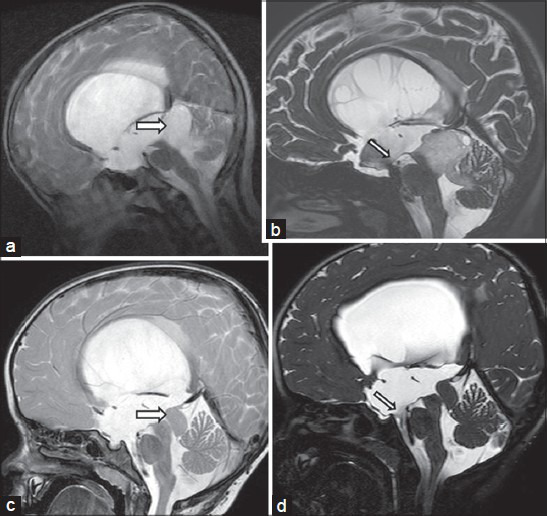

视神经下丘 脑胶质瘤 是一种典型的儿童幕上肿瘤。他们代表了全部中枢神经系统(CNS)肿瘤的1%和全部儿童脑肿瘤的3%到5%。视神经下丘脑胶质瘤往往影响婴儿...